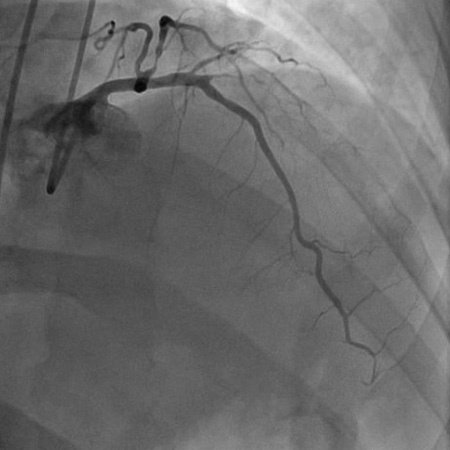

Angiograma (projeção craniana oblíqua anterior direita) em homem de 55 anos com história de 1 mês de angina ao esforço físico. A imagem mostra uma estenose proximal de 90% da artéria marginal obtusa 1 (o que explica a isquemia lateral do paciente), estenose proximal de 90% da primeira diagonal e oclusão subtotal de 99% da segunda diagonal (explicando a isquemia anterior e anterolateral do paciente)

Do acervo do Dr. S.D. Fihn; usado com permissão